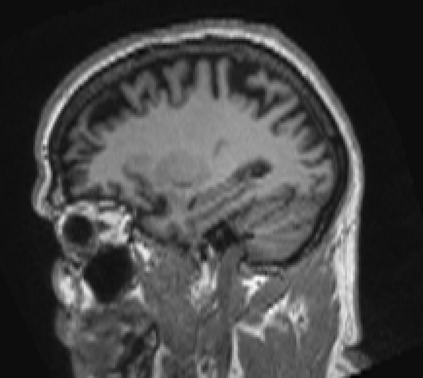

Due to various physical degradation factors and limited counts received, PET image quality needs further improvements. The denoising diffusion probabilistic models (DDPM) are distribution learning-based models, which try to transform a normal distribution into a specific data distribution based on iterative refinements. In this work, we proposed and evaluated different DDPM-based methods for PET image denoising. Under the DDPM framework, one way to perform PET image denoising is to provide the PET image and/or the prior image as the network input. Another way is to supply the prior image as the input with the PET image included in the refinement steps, which can fit for scenarios of different noise levels. 120 18F-FDG datasets and 140 18F-MK-6240 datasets were utilized to evaluate the proposed DDPM-based methods. Quantification show that the DDPM-based frameworks with PET information included can generate better results than the nonlocal mean and Unet-based denoising methods. Adding additional MR prior in the model can help achieve better performance and further reduce the uncertainty during image denoising. Solely relying on MR prior while ignoring the PET information can result in large bias. Regional and surface quantification shows that employing MR prior as the network input while embedding PET image as a data-consistency constraint during inference can achieve the best performance. In summary, DDPM-based PET image denoising is a flexible framework, which can efficiently utilize prior information and achieve better performance than the nonlocal mean and Unet-based denoising methods.